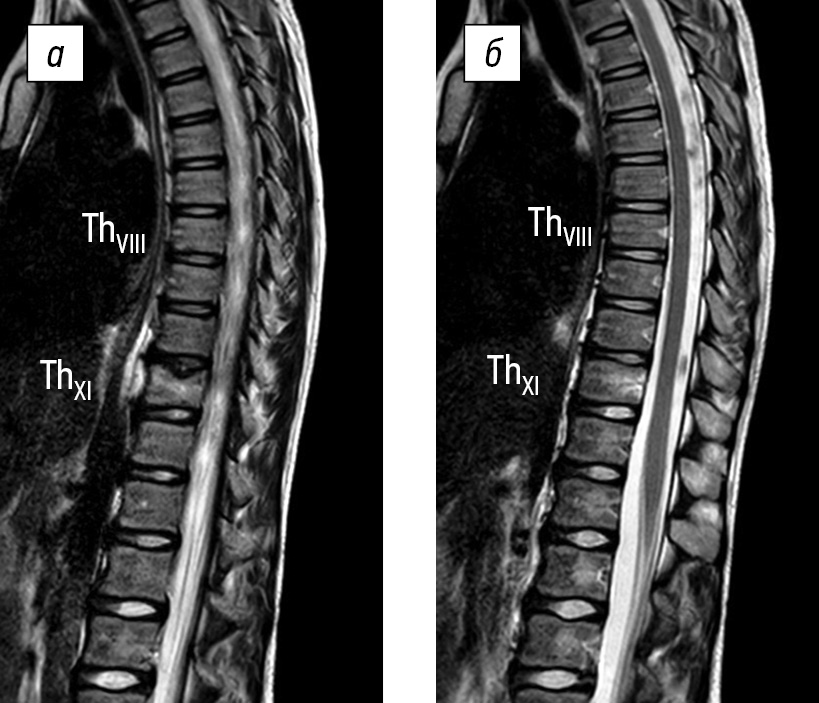

The final diagnosis was NBO, multifocal form. Therapy continued with nonsteroidal anti-inflammatory drugs. Ibandronic acid therapy was initiated at a starting dose of 1.5 mg, with subsequent infusions every 3–4 months at a dose of 2 mg, according to the decision of the off-label medical committee. The therapy scheme was borrowed from A. Dhanrajani and R.P. Khubchandani (2018) [12]. Ibandronic acid was administered to the child in 250 mL of 0.9% sodium chloride solution over 3 h using an infusion machine at a rate of 2 mL/min. The child received five consecutive infusions of ibandronic acid. The efficacy of the therapy was confirmed by imaging methods supplemented by clinical data. After the first administration of the medication, the mother observed an enhancement in the child’s overall health, an increase in motor activity, and a reduction in pain. The child tolerated the treatment regimen well, and no adverse reactions were detected either early or late. The laboratory results indicated a decrease in the ESR levels to normal. Radiation dynamics were evaluated sequentially after the second and fourth infusions. Following the fourth infusion of ibandronic acid, CT data revealed the complete restoration of the integrity of the bone structure of the anterior and posterior walls of the frontal sinuses. Inflammatory changes on the side of vertebral bodies were reduced after the second infusion, and the final subsidence of spondylitis was observed after the fourth infusion (Fig. 5). No new foci of destruction were observed during treatment.

Fig. 5. Magnetic resonance imaging of the thoracolumbar spine after four consecutive infusions of ibandronic acid. No signs of trabecular edema of the vertebral bodies are observed. In the central-left section of the ThXI vertebral body, deformation of the upper lamina is determined as a local indentation with a zone of fatty transformation of the bone marrow and areas of limited sclerosis. The height of the ThX–ThXI disk is moderately reduced without significant reduction in its signal